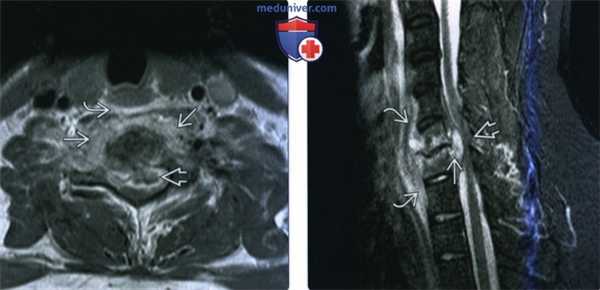

(Слева) Аксиальный срез, Т1-ВИ: аморфное низкоинтенсивное образование в области тела шейного позвонка и вентральной поверхности длинных мышц шеи. Паравертебральная флегмона стала следствием спондилодисцита.

(Справа) Аксиальный срез, Т2-ВИ: гетерогенное жидкостное образование в толще правой поясничной мышцы. Оно окружено толстой неправильной формы гипоинтенсивной стенкой, центральная часть отличается гиперинтенсивностью сигнала. Правая поясничная мышца с признаками диффузного усиления сигнала вследствие отека.

(Слева) Аксиальный срез, Т1-ВИ FS с КУ: ярко контрастирующееся гетерогенное паравертебральное жидкостное образование, окружающее переднюю и боковые поверхности тела поясничного позвонка. Накапливающие контраст ткани располагаются в непосредственной близости к аорте.

(Справа) Фронтальный КТ-срез: справа определяется паравертебральный абсцесс, сформировавшийся на фоне спондилодисцита. В полости абсцесса виден катетер. Гиперденсное внутреннее содержимое абсцесса может представлять собой продукты распада крови и гной.